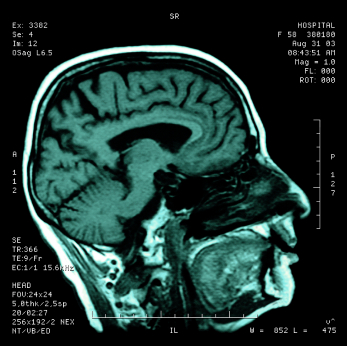

A lecture about Magnetic Resonance Imaging (MRI) and its new applications will occur on May 1. William G. Bradley, Jr., MD, PhD, professor and chair of UC San Diego’s Department of Radiology and an alumnus of UC San Francisco, will return to campus as the 2014 Margulis Alumnus Lecturer.

Bradley will present “MRI Over the Next Decade: Quo Vadis?” He will discuss some new MRI applications including faster scanning using parallel imaging and compressed sensing, intraoperative MRI, MR-guided focused ultrasound, hyperpolarized C-13 MR spectroscopy and hand-held MRI.

While at UCSF, Bradley first became involved in magnetic resonance imaging, initially “translating" the physics of MRI for other radiologists. His subsequent research has been focused on MRI of flow phenomena, hemorrhage, stroke, MS, and normal pressure hydrocephalus as well as other topics involving MRI of the brain.